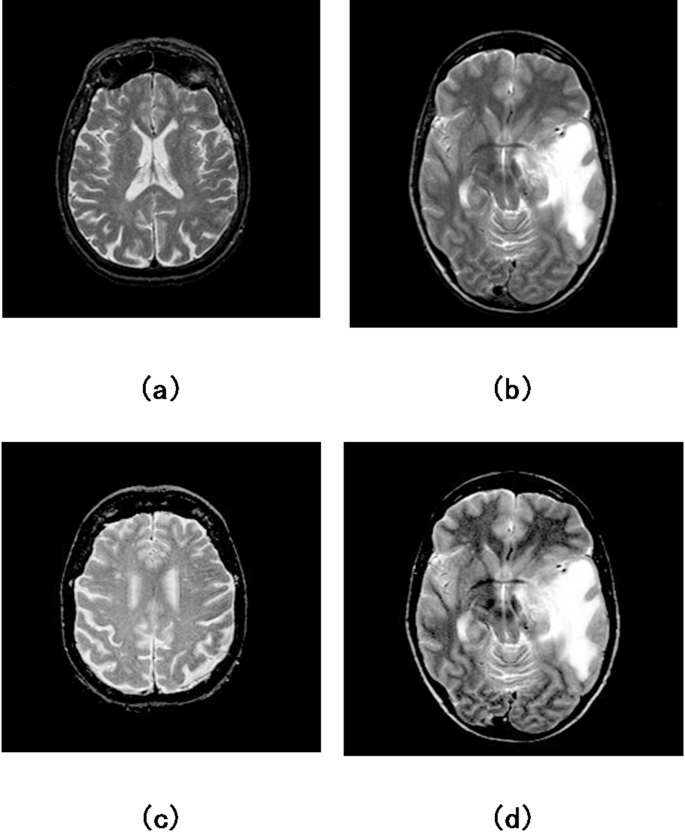

where \(\:I(m,n)\) is the original image; L is the dimensions of the image; G and \(\:\widehat{G}\) denotes the gradient along \(\:m\) and \(\:n\) direction; N illustrates the normalization factor; \(\:h(m,n)\)is the modified Gaussian function; ‘\( * \)’ indicates the convolution operator; \(\:\xi\:\)is an arbitrary constant which controls the brightness and contrast of an image. In the TSSR method, the parameter \(\:\xi\:\) controls image brightness and contrast. In this work, \(\:\xi\:\) = 1.5 is selected after evaluating several brain MRI images to enhance tumor visibility without introducing noise or edge artifacts. This value preserved anatomical detail while improving contrast between healthy and abnormal regions. Our choice is consistent with prior studies28, which recommend values between 1.2 and 2 for effective MR image enhancement. The effectiveness of β = 1.5 is visually supported in Fig. 2. It was observed that the TSSR method enhances the visual details of the tumor-affected region when compared to the original images. Consequently, the proposed model demonstrates improved effectiveness differentiating tumors in enhanced MR brain images. After that, decompose the enhanced image into low and high-frequency components using the EWT. Algorithm 1 represents the pseudo-code of the suggested enhanced model.

Contrast enhancement: (a,b) Original images; (c,d) enhanced images.